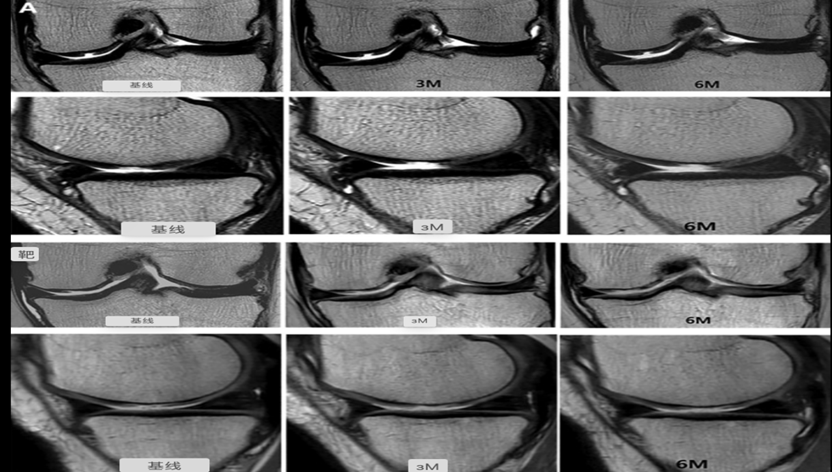

JOINTSTEM的实验,在12名患者中关节内注射了MSC,结果与其他12名接受生理盐水溶液的患者(对照组)进行比较。据作者称,注射MSC可以促进患者骨骼功能的恢复,而且减轻了疼痛,没有副作用[2]。

注射MSC可以促进软骨生长恢复